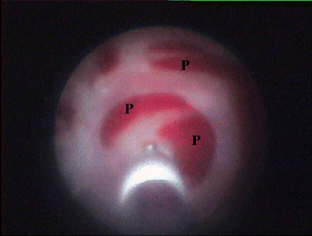

Fig. 1

Fig. 2

Fig. 3

Fig. 4